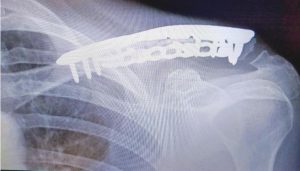

"In the winter of 2012 I suffered a fracture in the navicular bone of my left foot. Coming from an active lifestyle characterized by explosive and aggressive movements, I have experienced many broken bones. My surgeon proposed a multilayered plan of action that would attack the problem from both the mechanical and biological ends, including a titanium screw implant, bone marrow transplant, and stem cell transplant aimed at pulling the separated bone together and regenerating damaged tissue."